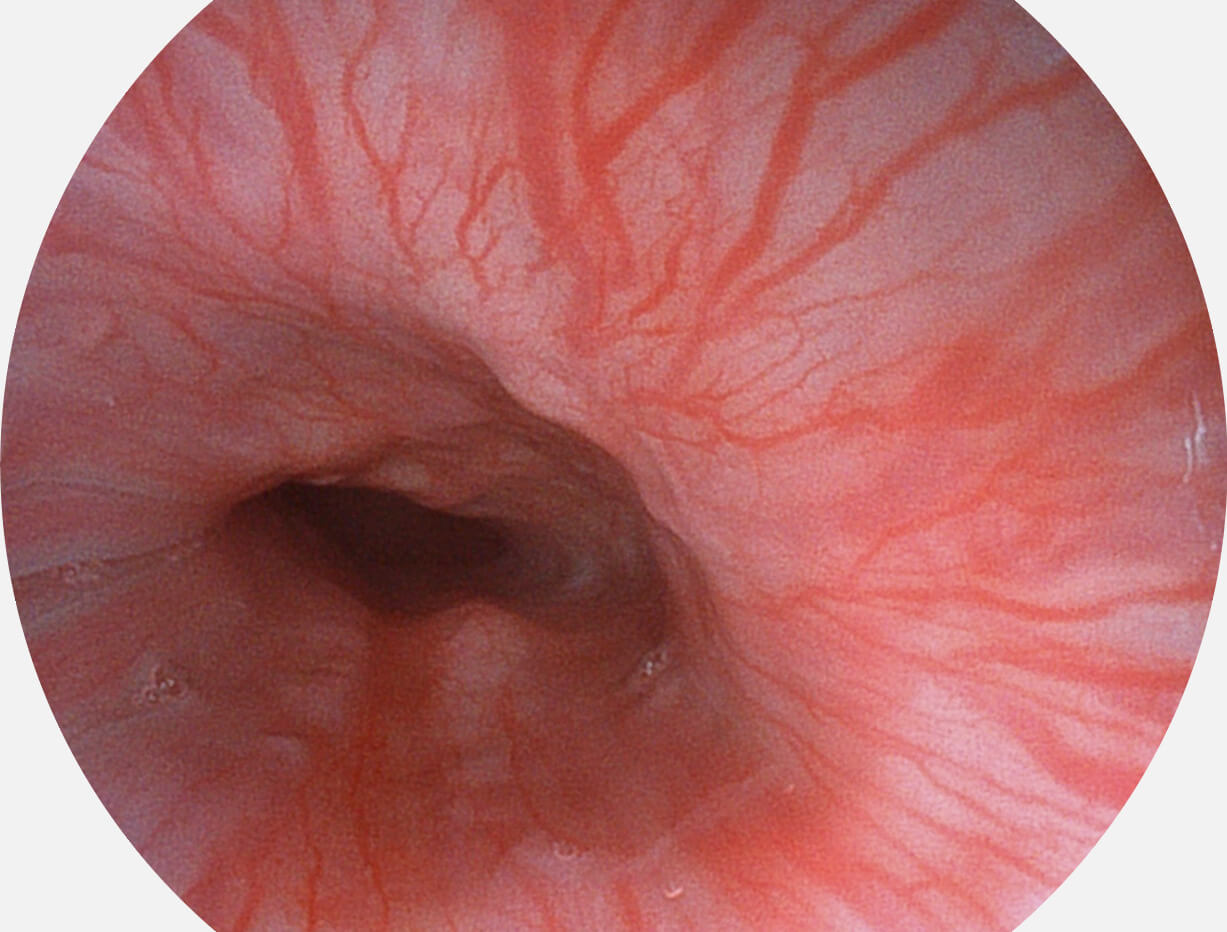

图像具有高亮度、高黏膜血管颜色对比度的特点,且不改变粘液、食物残渣、粪便的基本颜色,可在中远景下进行观察,助力消化道早期疾病的诊断。

• 白光图像 SFI图像